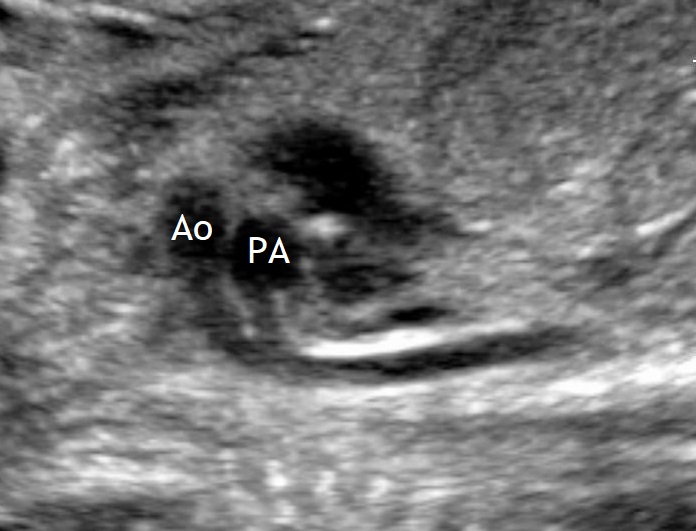

Below a case of complete TGA (d-TGA) detected prenatally.